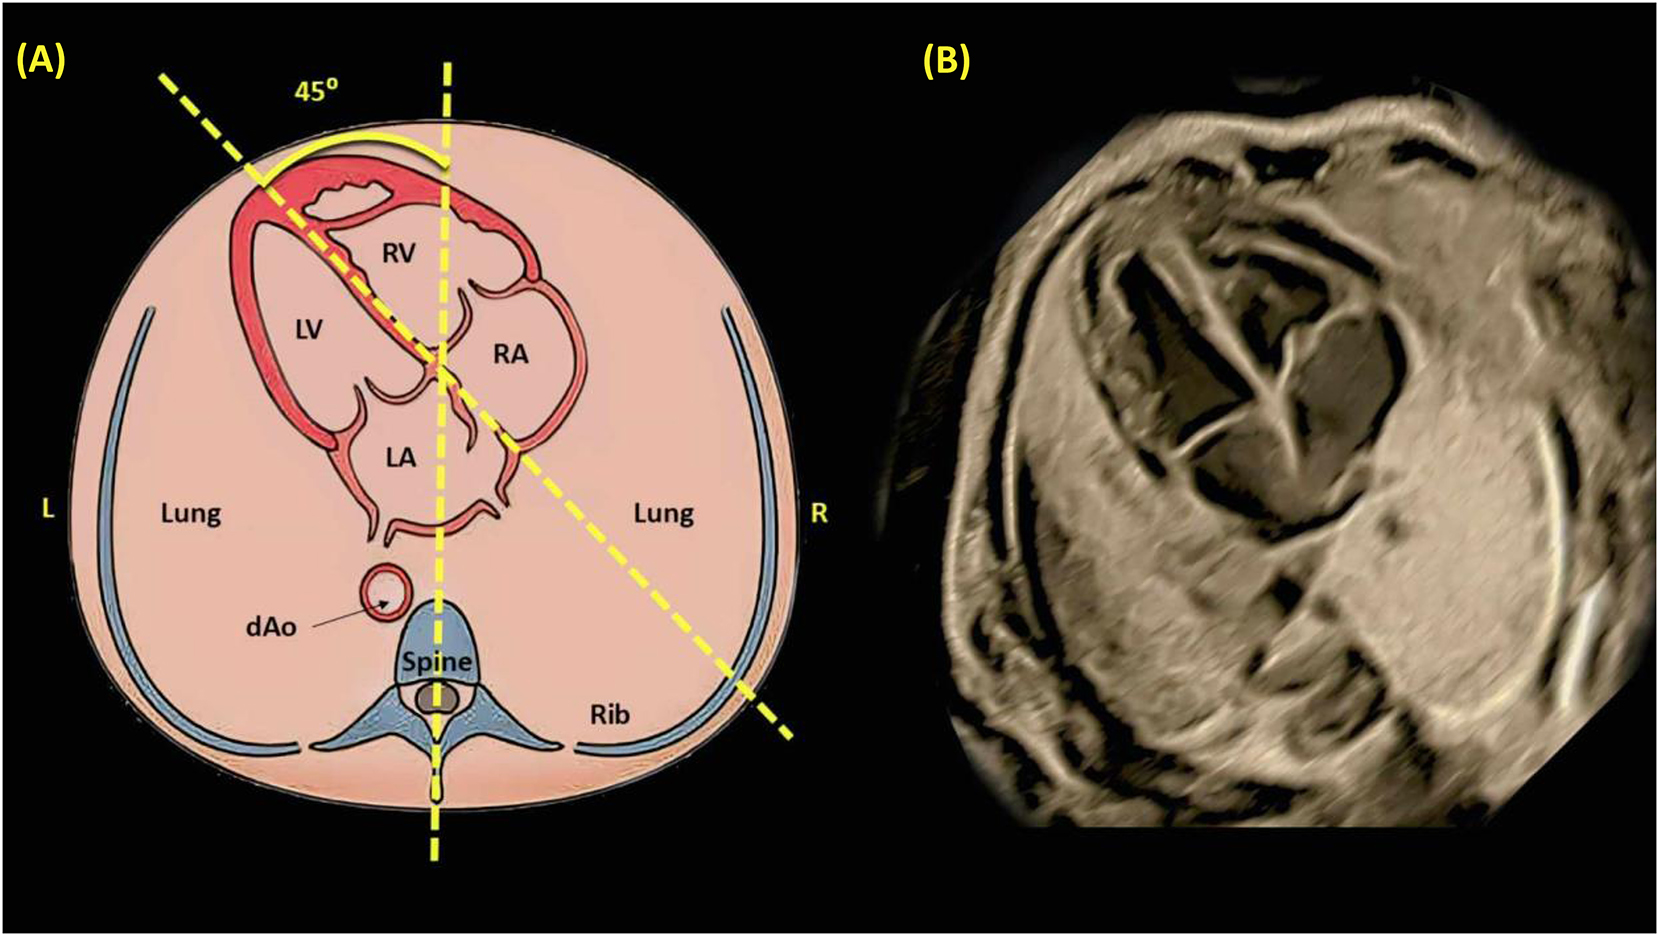

Evaluating fetal situs involves identifying the right and left sides to establish normal abdominal and cardiac orientation; transverse ultrasound sweeps confirm that both the stomach and heart are correctly positioned. Abdominal situs verification checks that the stomach, descending aorta, and inferior vena cava align properly relative to the spine, typically correlating with atrial situs solitus. In the four-chamber view, the heart should occupy about one-third of the chest cavity with a long-axis orientation of roughly 45° (±20°); structural deviations may indicate underlying CHDs, necessitating further imaging [3], 4], 9], 11], 24]. Figures 9–11, respectively, illustrate the assessment of fetal abdominal situs using grayscale and Doppler ultrasound, evaluation of fetal cardiac position and axis, and key components of the four-chamber view essential for detecting CHDs [9], 11], 16], 18], 23], 24]. One such structural anomaly is an atrial septal defect (ASD), which may be suspected in the four-chamber view and confirmed through advanced modalities such as STIC 4D ultrasound. Figure 12 illustrates a clear case of ASD, showing a persistent opening in the atrial septum that enables abnormal blood flow between the left and right atria. This dynamic imaging provides precise anatomical detail – including the size and location of the defect – and plays a crucial role in prenatal diagnosis, perinatal risk assessment, and postnatal management planning (Figure 13).

Illustrates the determination of cardiac position and axis through a schematic diagram (A) and a corresponding grayscale ultrasound image (B). An imaginary line is drawn from the spine at the back to the sternum at the front, dividing the thorax into two equal halves, left (L) and right (R). In a normal fetal heart, the majority of the heart is located on the left side, with the cardiac apex oriented towards the left at an angle of 45±20° relative to the anteroposterior axis of the chest. dAo refers to the descending aorta; LA, left atrium; LV, left ventricle; RA, right atrium; and RV, right ventricle [3], [4], [5, 9], 11], 24], 65], 66].](/document/doi/10.1515/jpm-2025-0037/asset/graphic/j_jpm-2025-0037_fig_010.jpg)

Illustrates the determination of cardiac position and axis through a schematic diagram (A) and a corresponding grayscale ultrasound image (B). An imaginary line is drawn from the spine at the back to the sternum at the front, dividing the thorax into two equal halves, left (L) and right (R). In a normal fetal heart, the majority of the heart is located on the left side, with the cardiac apex oriented towards the left at an angle of 45±20° relative to the anteroposterior axis of the chest. dAo refers to the descending aorta; LA, left atrium; LV, left ventricle; RA, right atrium; and RV, right ventricle [3], [4], [5, 9], 11], 24], 65], 66].